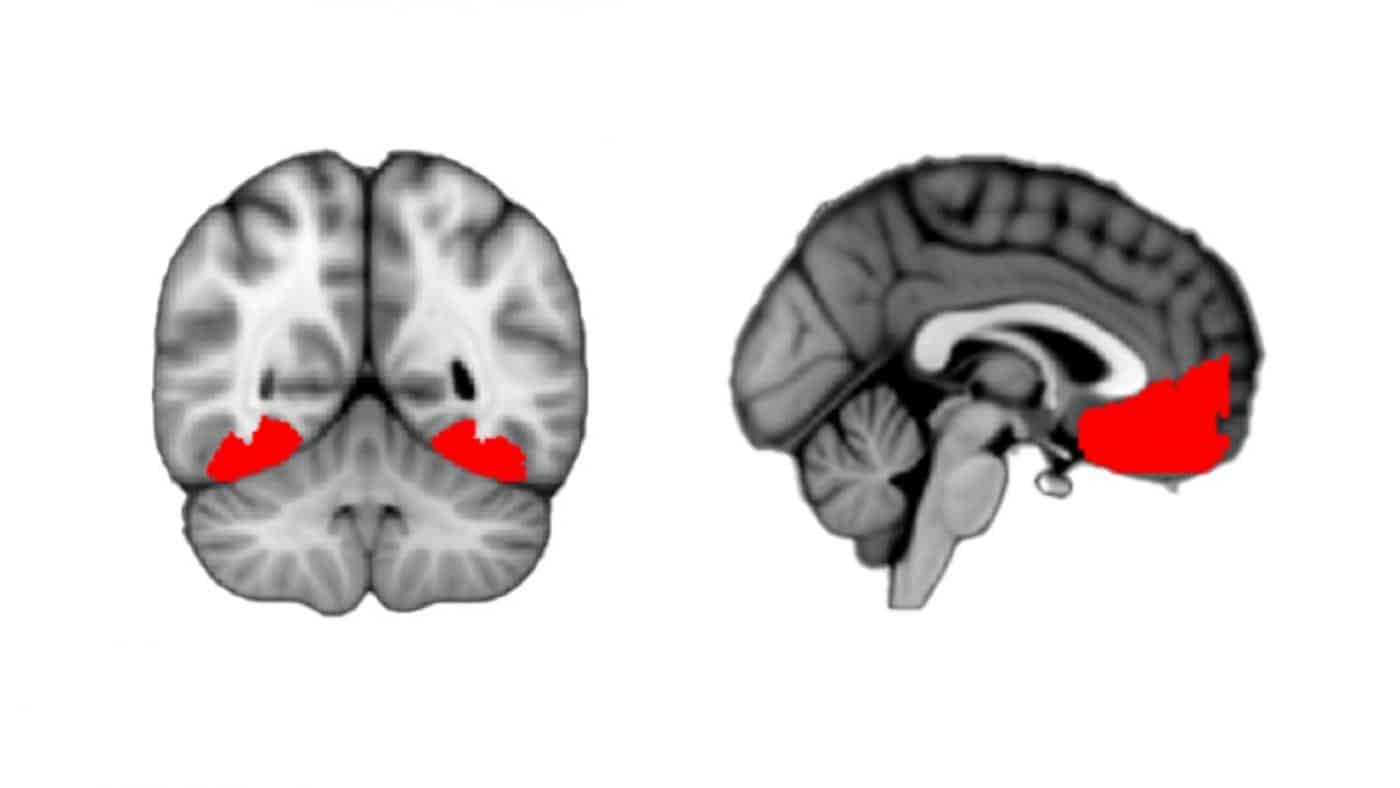

Сканы мозга. Показаны участки в переднем и заднем отделах, которые активизируются у любознательного человека  / © Gottlieb Lab/Columbia’s Zuckerman Institute

Ученые показали, что происходит в мозгу любознательного человека   Биология

Если человек не может однозначно интерпретировать какое-то визуальное явление, у него возникает желание рассмотреть его получше. Американские ученые впервые продемонстрировали, что происходит в этот момент в мозге.